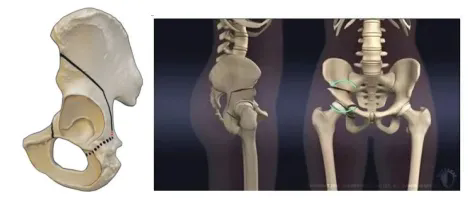

如果患者已無法通過保守治療DDH,那么外科手術矯形將成為治療早中期DDH唯一有效的辦法。治療DDH的矯形手術種類多樣,1988年以瑞士伯爾尼大學Ganz教授發明的Ganz截骨術(髖關節周圍截骨術(PAO)),因其術中能夠有效保護骨盆環的完整性,擁有良好的術后恢復效果,漸已成為DDH手術治療的主流術式。

髖臼周圍截骨術模擬圖